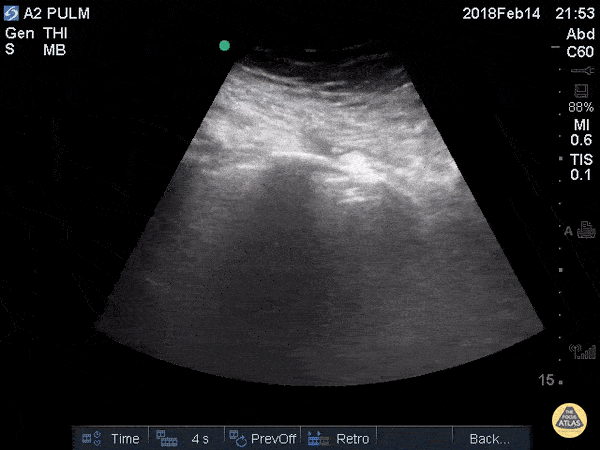

Pulmonary - Lung Point

29F in motor vehicle accident w/ right hemo/pneumothoarx. Lung point is demonstrated marking the transition of normal pleural to pneumothorax. This is the most specific sign of pneumothorax. Greg Powell, MD